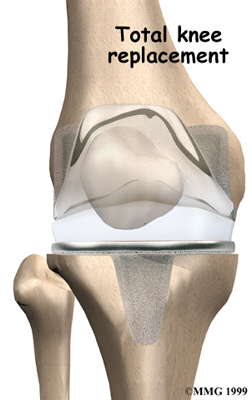

Artificial Knee Replacement

An artificial knee replacement is the ultimate solution for advanced knee OA.

Surgeons prefer not to put a new knee joint in patients younger than 60. This is because younger patients are generally more active and might put too much stress on the joint, causing it to loosen or even crack. A revision surgery to replace a damaged prosthesis is harder to do, has more possible complications, and is usually less successful than a first-time joint replacement surgery.

Related Document: FYZICAL Ocoee's Guide to Artificial Joint Replacement of the Knee